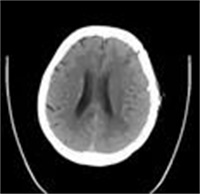

专家们为其复查颅脑CT显示:肿瘤已十分巨大,伴有少量出血,而且中线偏移近2cm,病情十分危急,刘大爷随时会有生命危险。家属更是没想到,怎么短短不到一个月的时间,病情进展加重的这么快?是否治疗?如何治疗?刘大爷的老伴儿和儿女们犹豫不决。

看到病魔不仅快要击垮患者,也快要击垮了患者的家庭,神外二病区主任金林耐心向患者家属解释:“胶质母细胞瘤是中枢神经系统最常见的、恶性程度最高的星形细胞瘤,属于恶性肿瘤。虽然病情不容乐观,但我们一起努力,争取让大爷苏醒过来…”。随后,金林主任详细介绍了治疗计划,通过手术,解决脑疝问题,取到颅内占位的确切病理结果,并进行综合治疗。取得家属同意后,手术开始。金林主任和他的手术团队历时5小时,顺利将患者的瘤体完整切除。术后CT可见,刘大爷的脑疝解除了,瘤体也切除了。